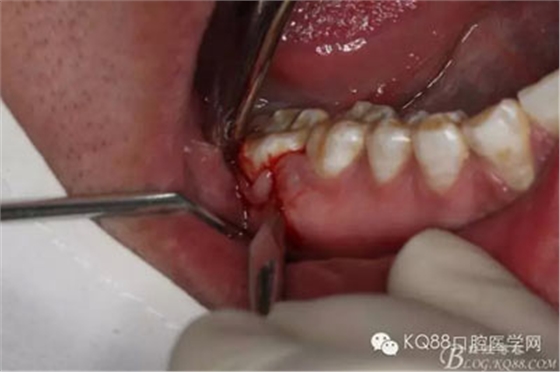

圖9.不斷的耐心去骨,發(fā)現(xiàn)48被下方的囊性改變趕到舌側(cè)。

圖13.把48干掉,繼續(xù)戰(zhàn)斗,摘除下方囊腫,結(jié)果翻瓣超過(guò)前庭溝時(shí),發(fā)現(xiàn)頰側(cè)骨板缺失,與48牙槽窩完全貫通

注意看:骨間隔上方是48牙槽窩,下方是囊腔。有點(diǎn)后悔翻瓣有點(diǎn)過(guò)淺了。

圖14.徹底清理囊腔內(nèi)的上皮組織,頰側(cè)骨壁缺失嚴(yán)重。